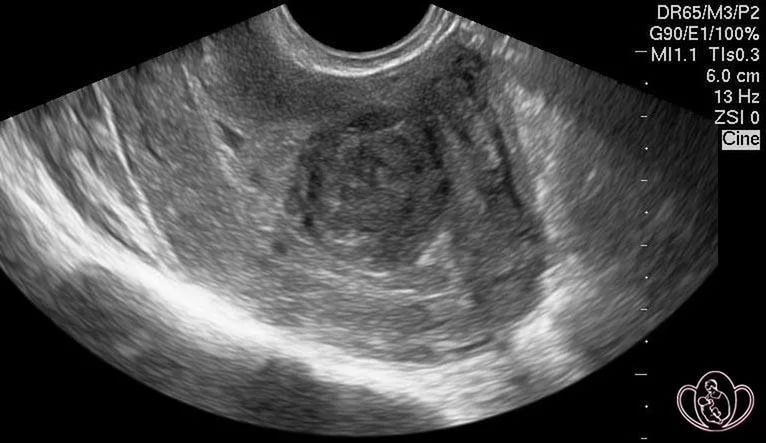

Как проводится диагностика рабдомиомы матки?

Диагностика рабдомиомы матки обычно включает ультразвуковое исследование, которое позволяет визуализировать опухоль и оценить ее размеры. В некоторых случаях может потребоваться магнитно-резонансная томография (МРТ) для более детального изучения. Также может быть проведена биопсия для исключения злокачественного процесса.